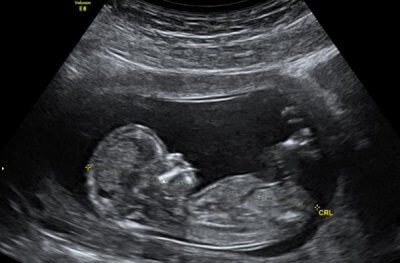

Bei der Modellierung griffen die Ärzte der in Rio de Janeiro betriebenen „Clinica de Diagnóstico por Imagem“ auf zwei altbewährte Verfahren zurück – die Magnetresonanztomographie (MRT), die auch als Kernspintomographie bezeichnet wird, und die Sonographie (Ultraschall). Diese beiden Verfahren wurden jetzt miteinander kombiniert und ermöglichen es Ärzten, 3D-Bilder vom ungeborenen Kind zu erzeugen, die mit einer handelsüblichen Oculus Rift VR-Brille betrachtet werden können.

Mit dem neuen Verfahren werden die Gebärmutter und das ungeborene Kind gescannt und die so gewonnenen Daten zu einem vollständigen 3D-Modell des sich entwickelnden Babys zusammengesetzt.

Den Forschern zufolge wurden beide Verfahren kombiniert, wenn die Ultraschall- und MRT-Bilder nicht klar genug erschienen. Mit den neuen detaillierten 3D-Modellen ist es Ärzten nunmehr möglich, Probleme zu diagnostizieren, mit denen das Kind nach der Geburt konfrontiert sein könnte. Die Ärzte könnten beispielsweise schon vor der Geburt sehen, wenn die Atemwege des Fötus blockiert seien und entsprechende Maßnahmen einplanen. Auch eventuelle Missbildungen lassen sich so vorab herausfinden.

Der Oculus Rift bietet deutlich schärfere fetale Bilder als der Ultraschall und die MRT. Eventuell ist es später sogar möglich, die Bilder in 3D-Drucke umzuwandeln, die den Eltern dann als Andenken mitgegeben werden könnten. Das britische Unternehmen „baby:Boo“ bietet bereits derartige Leistungen.